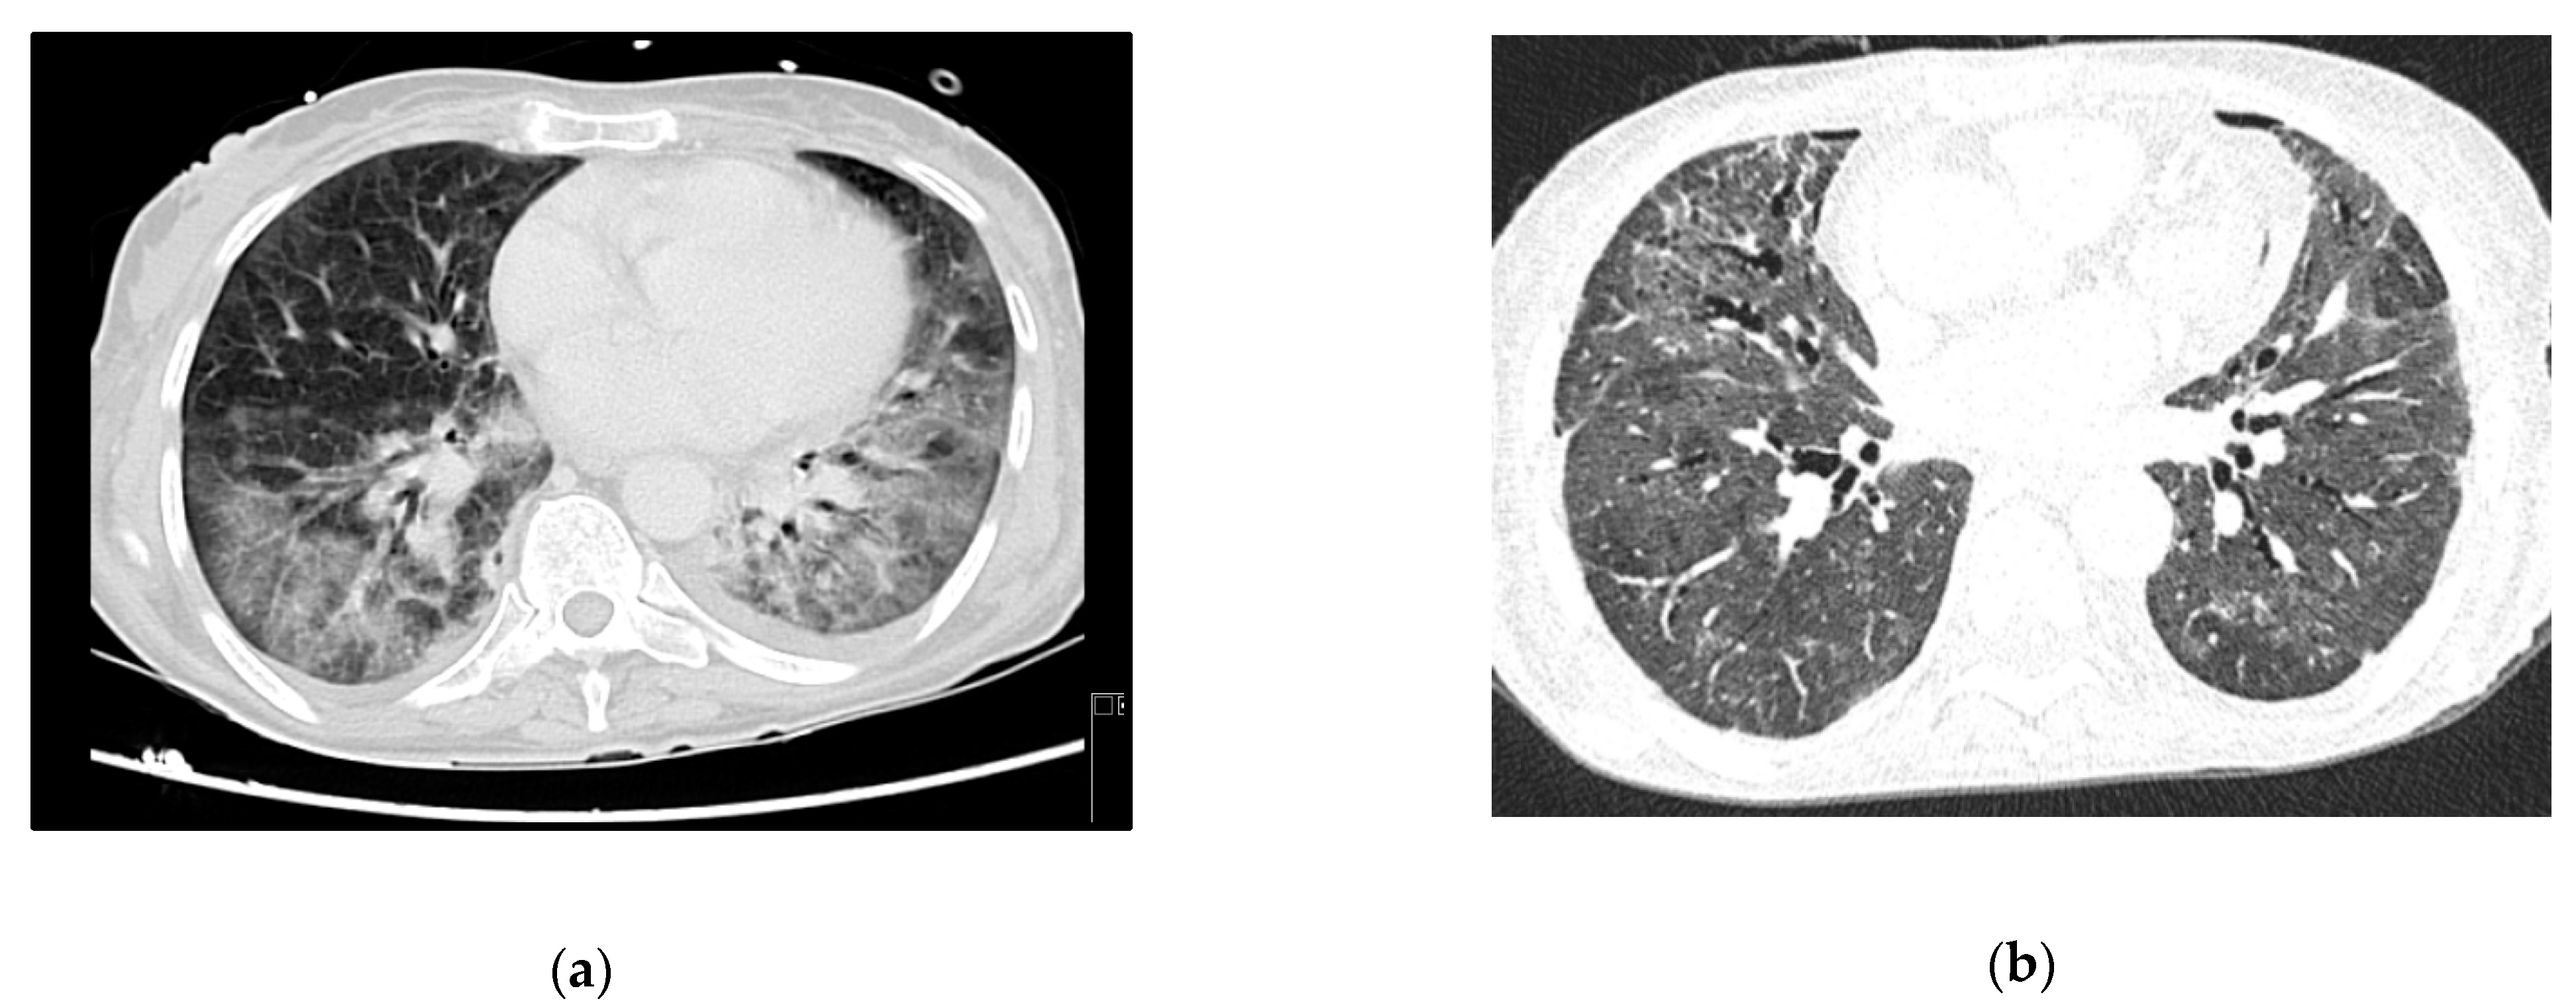

A 53-year-old woman, with no relevant medical history so far, was brought to the ER due to a two-month history of progressive psychomotor slowness and confusion, which had worsened in the week before. At physical examination, she was agitated and febrile. Head CT scan showed some intra-axial lesions in the left frontal and temporal lobes. The cerebral spinal fluid (CSF) had mild pleocytosis and moderately elevated proteins. The serology for HIV was positive, and the nucleic acid test of the CSF was positive for toxoplasma gondii. She was admitted in the ICU with a de novo diagnosis of HIV infection, with severe immunosuppression (CD4+ count 28 cells/mm3), clinically manifested as cerebral toxoplasmosis. On day 3, she began coughing, with respiratory hypoxemic insufficiency and bilateral diffuse glass opacities on chest-CT scan (Figure 3a). The presumptive diagnosis of PJP was posteriorly confirmed with both direct dye-examination and PCR positive for P. jirovecii in BAL. She was treated with TMP-SMX for both PJP and cerebral toxoplasmosis. Following one week of appropriate medical treatment, the patient had a favorable response, and was discharged to the ward for further care.

Figure 3.

Case 3 thoracic CT-scan at diagnosis (a) and follow-up (b).

At the end of the month, she was readmitted to the ICU because of respiratory failure and elevated lactate. Respiratory secretions and gastric aspirate were both negative for tuberculosis. Other microbiology tests (including blood serologies for other common opportunistic agents) were also negative. She repeated chest-CT, and had severe deterioration in the lung opacities, with bilateral consolidation described as possible ARDS and/or nosocomial infection. As she showed no signs of clinical improvement despite corticosteroids and High Flow Oxygen Therapy (HFOT), she was intubated, had a repeat bronchofibroscopy and started broad spectrum antibiotics.

The patient developed septic shock and ARDS with refractory hypoxemia and she was put on VV-ECMO. The indirect immunofluorescence was positive for P. jirovecii in BAL. She completed 21 days of treatment for PJP and 7 days of piperacillin- tazobactam, with respiratory improvement. ECMO was stopped after 12 days.

Persistent fever and elevated inflammatory markers ensued, with isolation of multidrug-resistant Pseudomonas aeruginosa in respiratory secretions. Chest X-ray confirmed lobar nosocomial pneumonia. She started a targeted antibiotic course with cefepime, with good clinical, analytical, and radiological response. Roughly one week later, she was extubated to non-mechanical ventilation, and rapidly weaned off respiratory support to no oxygen supplementation. The evolution in her condition can be seen at the images in Figure 3b.

She was discharged to the ward after one month of ICU stay for muscular rehabilitation, already on antiretroviral therapy and free of acute infectious complications.